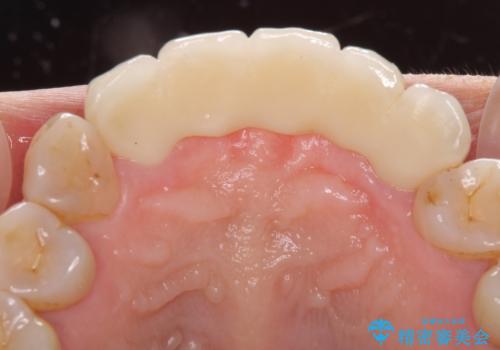

自然な仕上がりとするため、金属を使用しないオールセラミックブリッジにより補綴治療を行うこととしました。

装着されていたブリッジは、支台となっている歯と欠損している歯で色が大きく異なっていましたが、オールセラミックとしたことで、全体的に色調の整った仕上がりとなりました。

歯肉ラインがきれいに整い、患者様には大変満足していただきました。